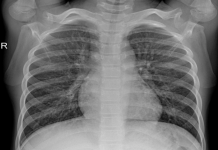

This dataset is formed by taking 25 images of COVID-19 from [35] in the first step. We then add another 75 non-Covid cases of chest X-ray image from [36]. It is important to note that these non-Covid (normal) cases might consist of other unhealthy conditions such as bacterial or viral infections, chronic obstructive pulmonary disease and even a combination of two or more. Accordingly, what we mean by a normal or non-Covid case does not necessarily infer a healthy lower respiratory system. Two images of covid and normal classes are shown in Fig. 2. Fig. 2(b) displays a normal (non- Covid) case, yet virally infected. All images in this dataset are accessible via this link: https://github.com/dara1400/Covid19-Xray-Dataset.

Figure 2: Two sample images from X-ray dataset.